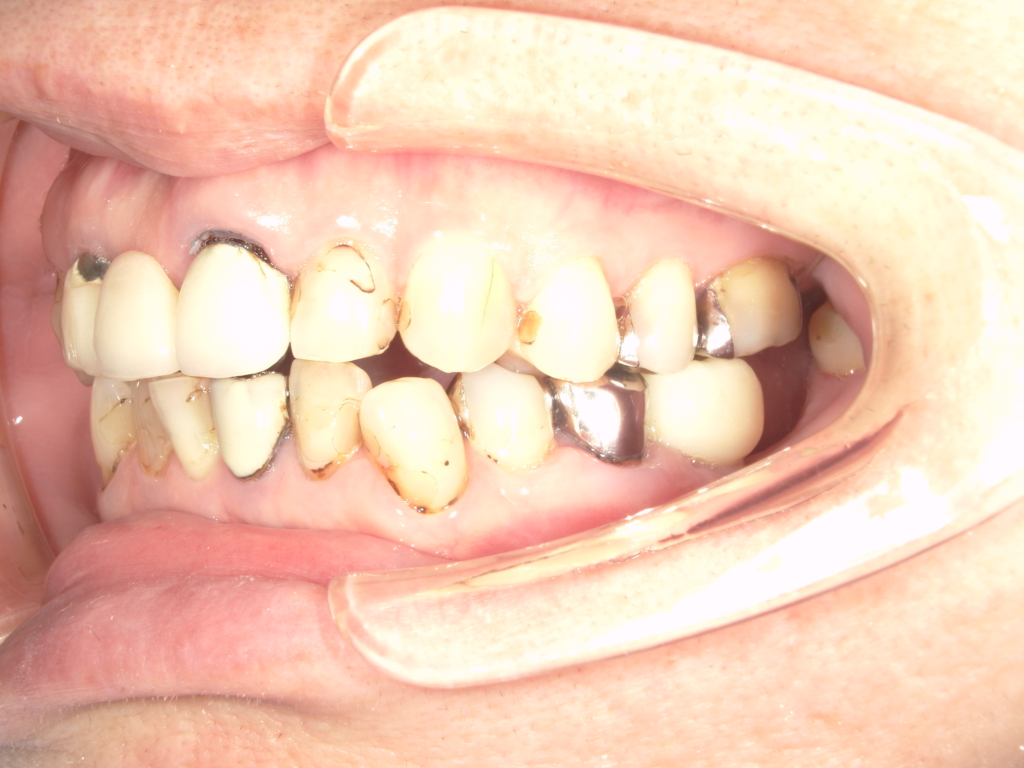

Y様インプラント実例 #44

左の上下の奥歯をインプラントで治療しています。

左下の奥歯は歯を抜くのと同時にインプラントの埋め込みを行っています。

被せものは上下、セラミックスで作っています。

治療前

治療後